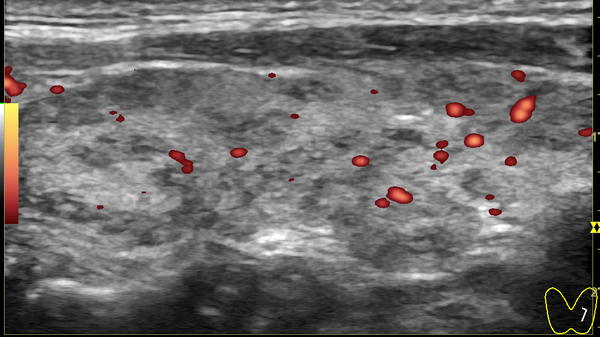

При проведении экспертного УЗИ в специализированной клинике узлов обнаружено не было. На снимке чётко видна структура железы.

На этом изображении центральной части левой доли светло-серая мелкозернистая область — это полноценная гормонообразующая ткань. Тёмные участки — это зоны, где идёт процесс разрушения ткани и её очистки клетками иммунной системы (лимфоцитами).

На обзорном снимке левой доли (правая выглядит аналогично) видно, что более 80% ткани имеет здоровый, светло-серый вид. Это означает, что железа обладает значительным резервом и способна самостоятельно обеспечивать организм гормонами, особенно если создать для этого благоприятные условия.

Заключение: Ультразвуковые признаки тотального диффузного процесса в щитовидной железе с увеличением правой доли (зоб 1-й степени), с умеренными явлениями разрушительных изменений в дольках и сегментах, сопровождающихся незначительной инфильтрацией лимфоцитами. Напряжённость ткани железы (по показателям кровотока) незначительно повышена с обеих сторон. Объём относительно полноценной гормонообразующей ткани составляет около 80–85%.